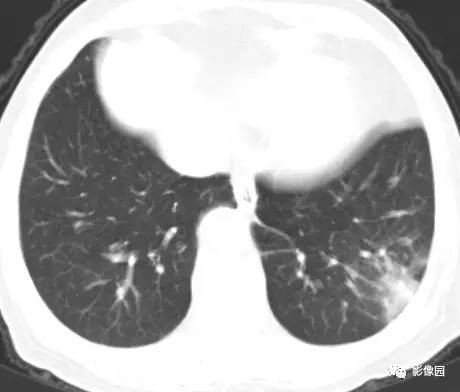

左下肺鳞癌1例CT

病史:女,77,体检发现左下肺占位5天。CT平扫肿物CT值约为40Hu,增强后约95HU 医学百科网 | YxBaike.Com

穿刺结果:(左下肺)部分肺组织:慢性支气管炎及支气管周围炎,肺泡间质纤维组织增生,个别支气管粘膜鳞状上皮化生,部分恶变,呈鳞状上皮原位癌结构,极个别区域有支气管壁早期浸润。 医学百科网 | YxBaike.Com